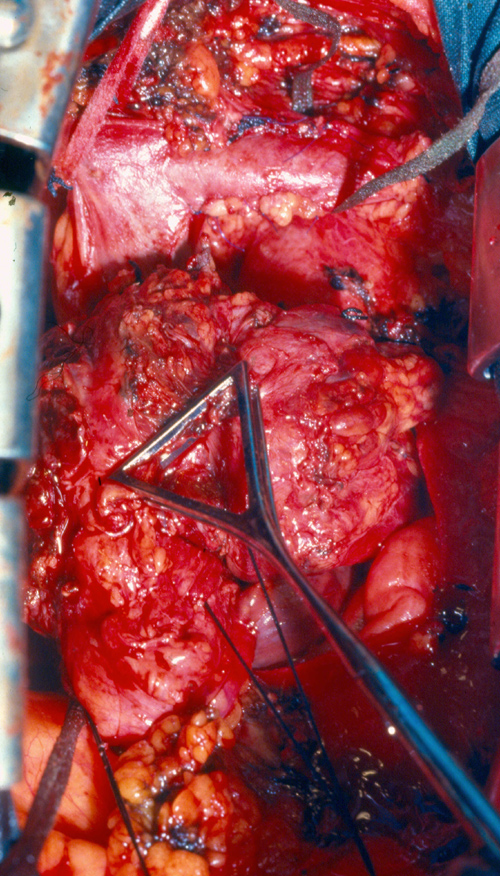

Surgical strategy and shunting techniques: Every effort should be attempted to reduce clamping time as much as possible, in particular when the SVC system is not completely occluded before the operation. It has been reported that up to 45 to 60 minutes of complete clamping is usually tolerated with the appropriate pharmacological support. For lung cancer resection, the vascular step should be always performed before any other reconstructive procedure of the airway. For mediastinal tumors involving the upper lobes, the dissection should be performed from the left to the right side; the right part of the excision is usually performed after vascular reconstruction, in particular when a lobectomy is required. Intravascular or extravascular shunts (Figure 5) may be used to reduce the effects of vascular clamping during resection and reconstruction of the SVC[4]. However, thrombosis of the shunt may occur; furthermore, these devices occupy space in the operative field making the anastomosis more difficult.

Figure Figure